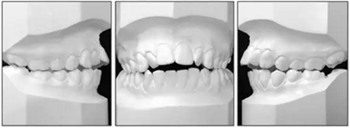

口內(nèi)分析顯示呈II類1分類錯合畸形,前牙開合2mm和覆蓋3mm(圖2)。左側(cè)的后牙存在反合。上牙弓擁擠度2.5mm,下牙弓擁擠度1mm。中線一致。下頜前牙區(qū)牙齦稍有退縮。